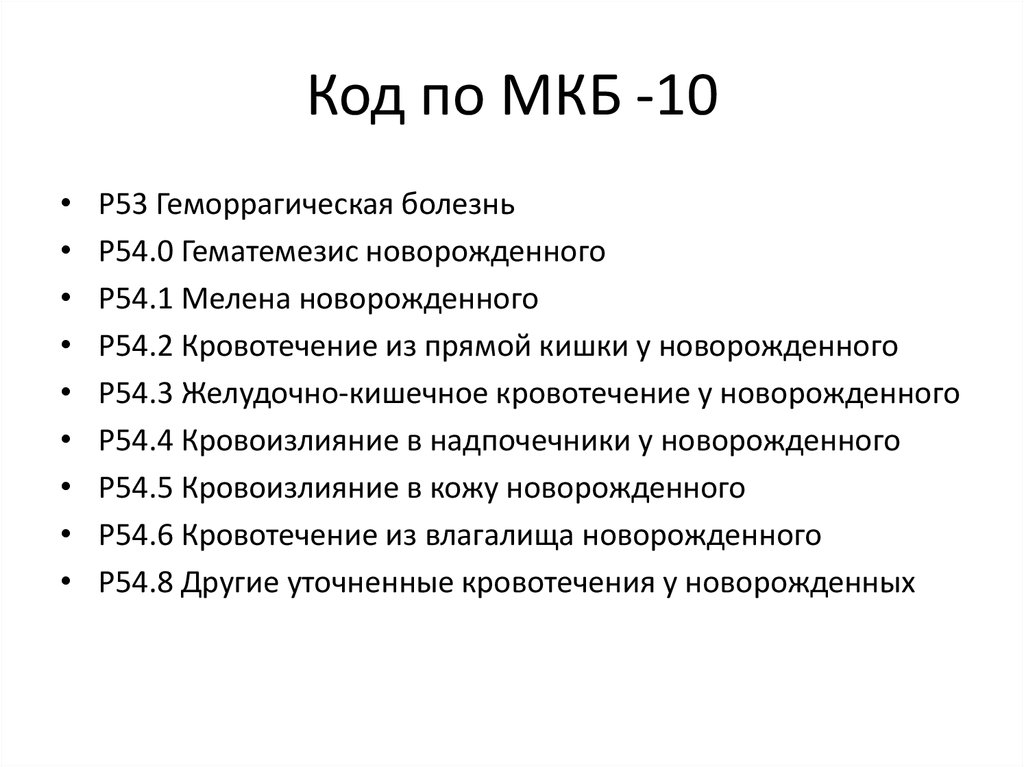

Код мкб 10 атерома головы

Код мкб 10 атерома головы 109 фото